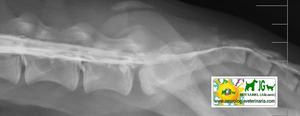

MIELOGRAFIA con inyección de contraste en el saco dural a nivel de L5 |